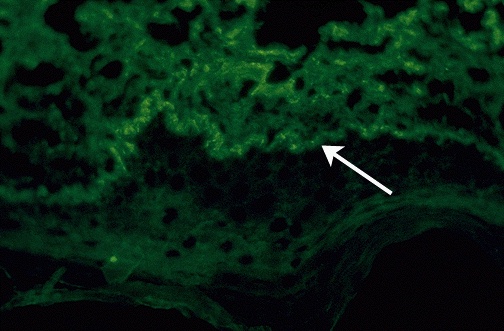

Immunofluorescence techniques can be applied to tissues taken via biopsy. Anti-human IgG tagged with FITC helps to identify these immune deposits at the dermal-epidermal junction in the skin of a patient with systemic lupus erythematosus.